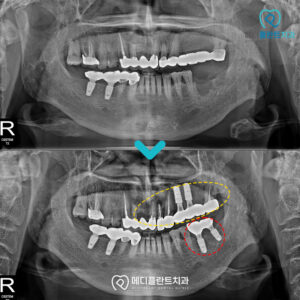

춘천수면치과 어르신분들도 편안하게! 유치가 탈락하고 맹출하는 영구치는 말 그대로 영구적으로 평생 사용해야 하는 치아입니다. 한 번 상실되면 더 이상 새로 자라지 않기 때문에 오랫동안 건강한 상태로 유지하기…